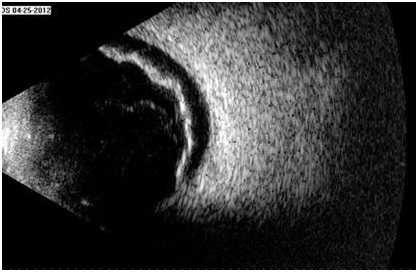

В лекции показаны возможности ультразвуковой диагностики в выявлении аномалий развития глазного яблока, стекловидного тела, сетчатой и сосудистой оболочек глаза, зрительного нерва (микрофтальм, персистирующая гиалоидная артерия, колобомы и пр.).

Рассмотрены врожденная и приобретенная патология хрусталика (аномалии, катаракты, дислокации), уделено внимание эхографическому изображению глаза после имплантации искусственного хрусталика, в том числе при развитии осложнений.

Представлена информация по ультразвуковому исследованию глаз с нарушением внутриглазной гидродинамики (глаукомы) и при миопии, включая её осложненные варианты, а также глаз после хирургического лечения отслойки сетчатки.